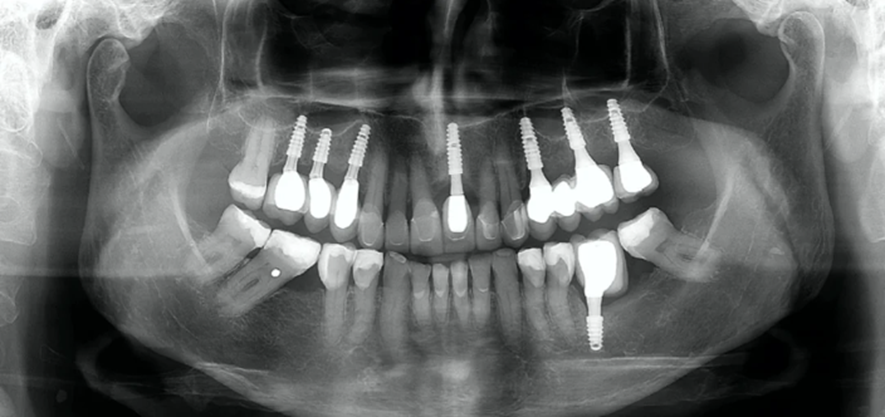

Embora muitos profissionais considerem arriscado colocar os implantes Cone Morse muito dentro do osso, eu acredito que um mergulho mais profundo destes implantes Cone Morse aumenta a previsibilidade do conjunto implante/prótese, favorecendo a saúde e estética peri-implantar. As figuras 5 e 6 ilustram um caso deste estilo.

Obviamente que mais pesquisas são necessárias para que possamos estabelecer um consenso sobre o quanto podemos colocar um implante Cone Morse dentro do osso. Contudo, devemos procurar respeitar as distâncias biológicas entre dentes e implantes e entre implantes. Assim como na dentição natural, os implantes também exigem um espaço livre de osso, a fim de que os tecidos moles possam se adaptar e este espaço parece estar nos pilares mais estreitos e longos.